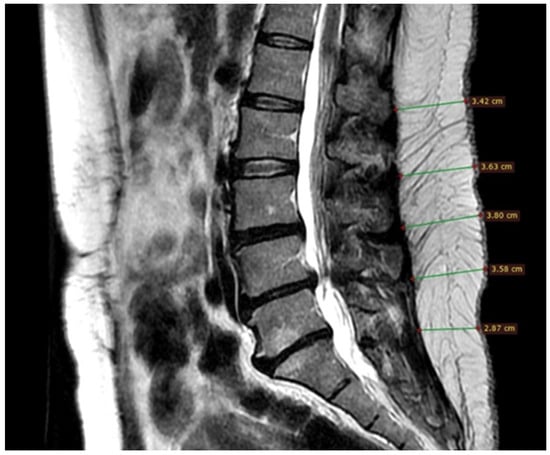

2.4. Image Mode

2.5. Subcutaneous Fatty Tissue Thickness Measurement